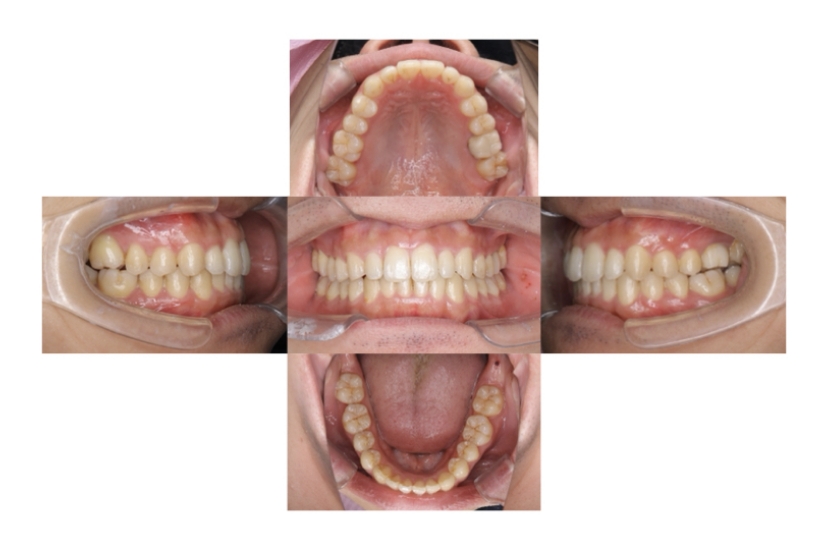

症例3

叢生

抜歯

ブラケット矯正

上下顎叢生(上下の前歯のガタガタ)のケースです。

装置はラビアル(上下表側)で、上下顎の小臼歯を4本抜歯を行っています。抜歯したスペースを使って、上下の前歯の後方移動と叢生(ガタガタ)の改善を行っています。

主訴 八重歯を治したい。

年齢・性別 25歳 女性

お住まいの地域 神奈川県川崎市

治療方針 抜歯スペースを利用して上前歯の叢生(ガタガタ)の改善

抜歯部位 上下顎左右第一小臼歯

使用装置 ラビアル(上下表側)、顎間ゴム

治療期間 1年11か月

治療回数 16回

リテーナー クリアリテーナー

BEFORE

AFTER